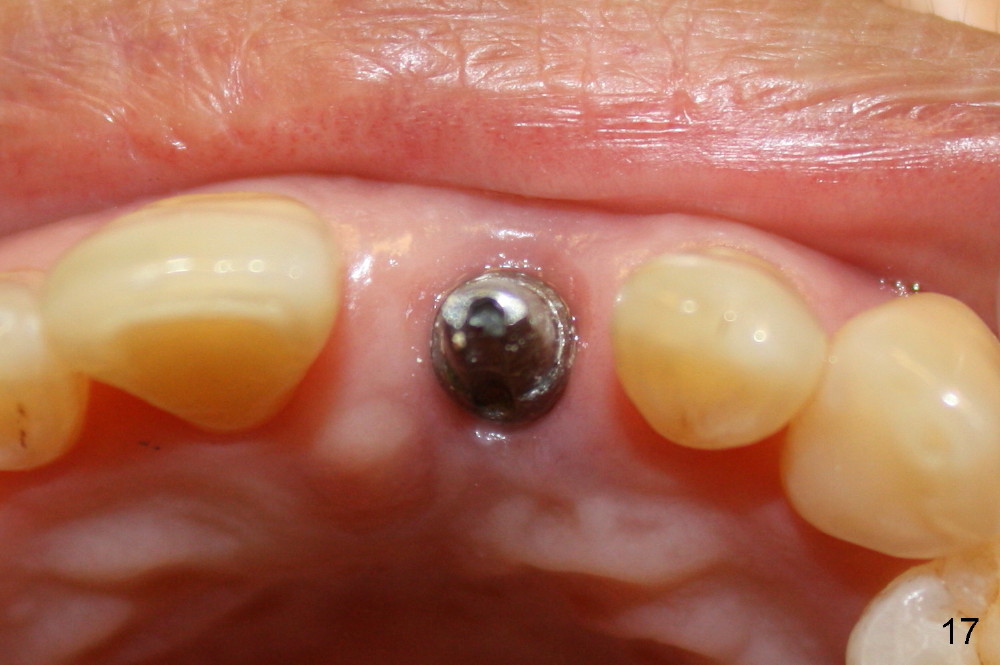

A 60-year-old lady had an abscess mesial to #9 six years ago (Fig.1,2 <), treated as a perio lesion by laser (Fig.3) and osseous surgery without bone graft (Fig.6, followed by CT exam revealing semi-circumferential bone loss (Fig.4,5). When the perio treatment failed, attention was paid to endo aspect (Fig.7-9). In fact the pulp was found to be vital when access to root canal therapy was made. As expected, the treatment failed again. The palatal fistula persisted. The infection was suspected to be a source of remote immediate implant site (#30). The tooth #9 was extracted. It appears that there is a semilunar crack line in the linguomesial root (Fig.12). When the socket healed 2 weeks post extraction (Fig.10), the #30 buccal defect was debrided with bone graft. There was no bone resorption 4 weeks post extraction (Fig.11); a 4.5x17 mm implant was placed (Fig.13-15). An immediate provisional was fabricated (Fig.16-18). Fig.19,20 were taken 3 months post implantation and 7 months post cementation, respectively. Dense bone forms around the implant coronally 4 years 5 months post cementation (Fig.21), while the gingiva is healthy palatally (Fig.22) and buccally (Fig.23).